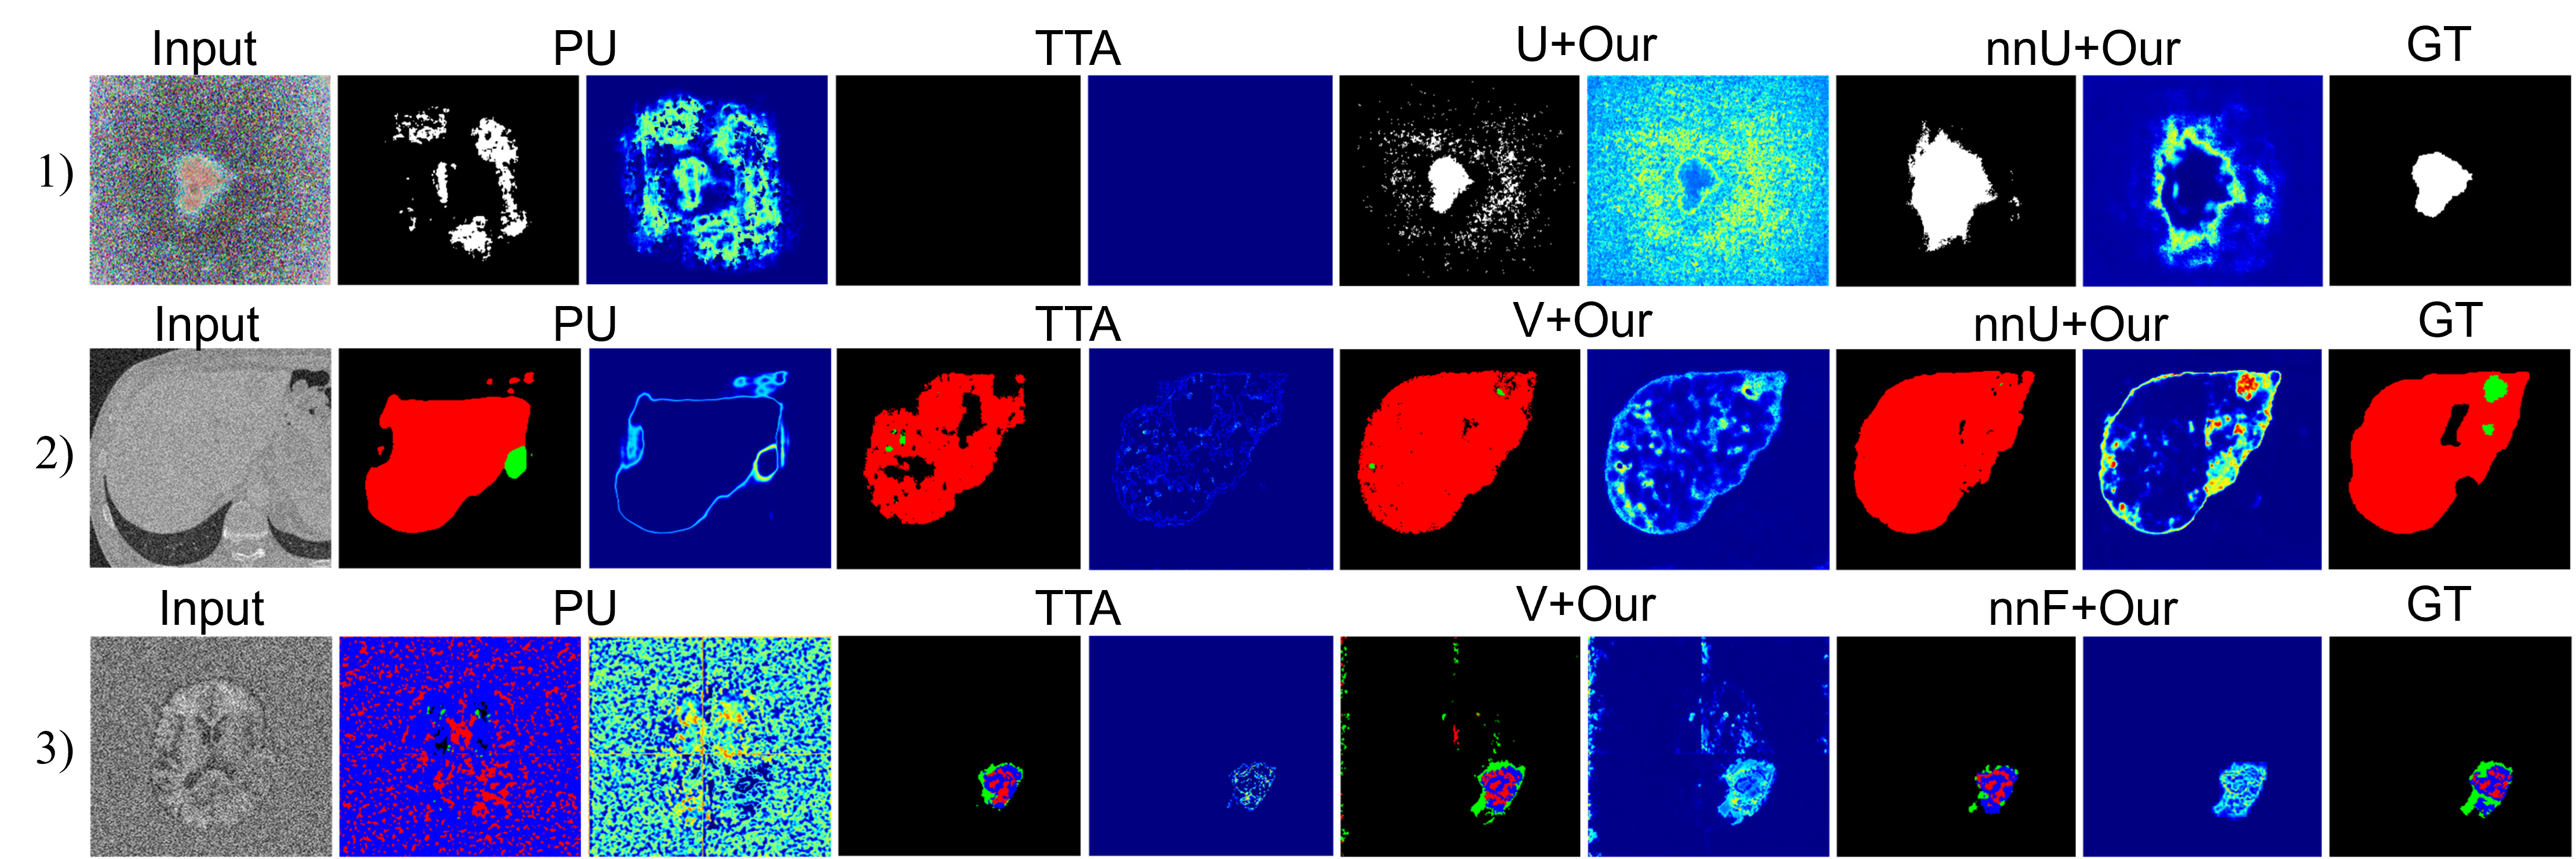

As shown in the Tab. I, the comparison results between DEviS and other U-Net variants under different Gaussian noise levels ratios are presented. Tab. I indicates a gradual degradation in performance for U-Net, AU-Net, V-Net, nnU-Net, and VM-UNet, particularly at higher mask ratios and noise levels. Upon applying DEviS, the results exhibit a certain degree of robustness to interference. When equipped with DEviS, U-Net demonstrates an average improvement of 10.6% and 8.9% in Dice metric under degraded conditions of Gaussian noise and random masking, respectively. Additionally, the generated uncertainty estimates, as illustrated in Fig. 2, can be utilized by researchers and clinicians to discern the unreliability of the data.

As shown in Tab. II, the comparison results of the ECE and UEO metrics between the proposed method and other uncertainty estimation methods are presented. It reveales that BQNAT, DU, PU, UE, and TTA methods were significantly affected by noise and masking, while the perturbation on U-Net, V-Net, nnU-Net, and VM-UNet methods was relatively minor after applying DEviS. A comparison of uncertainty estimation results using ECE and UEO metrics indicated that U-Net, V-Net, nnU-Net, and VM-UNet with DEviS achieved better uncertainty estimation. Visualizations of segmentation results and uncertainty estimation as shown in Fig. 2, demonstrate that the proposed DEviS method provides more reliable uncertainty estimation for target edges and the noised pixels.